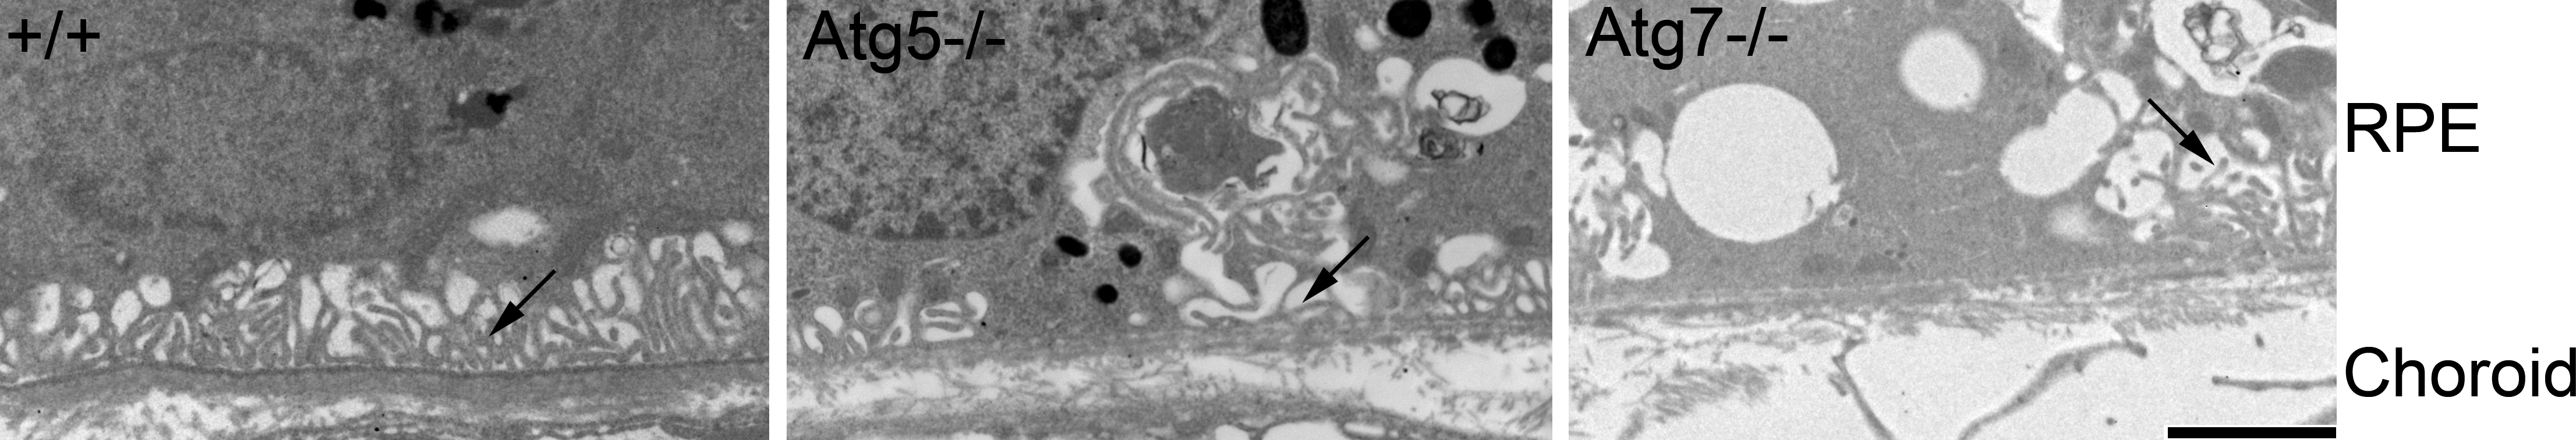

Figure 8. Diminished RPE basal infoldings in aged Atg5ΔRPE and Atg7ΔRPE mice. Representative electronic micrographs showing the RPE basal infolding area of 17-month-old wild-type (+/+), Atg5ΔRPE (Atg5−/−), and Atg7ΔRPE (Atg7−/−) mice. Note the scarce basal infoldings (arrow) in the Atg5ΔRPE and Atg7ΔRPE mice. Scale bar = 2 µm.